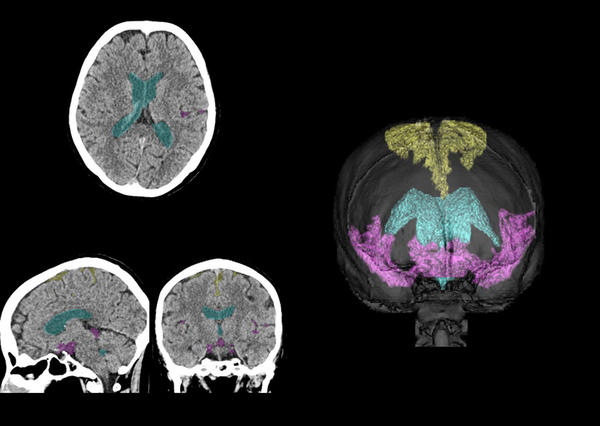

CT画像上で本技術を用いて脳脊髄液腔の各領域を抽出した例

高位円蓋部・正中のくも膜下腔,脳室,シルビウス裂・脳底槽を領域ごとに検出することで,体積比の算出が可能となり,ハキム病の診断に重要なDESHの判定を支援する。

黄色:高位円蓋部・正中のくも膜下腔,水色:脳室,赤紫色:シルビウス裂・脳底槽